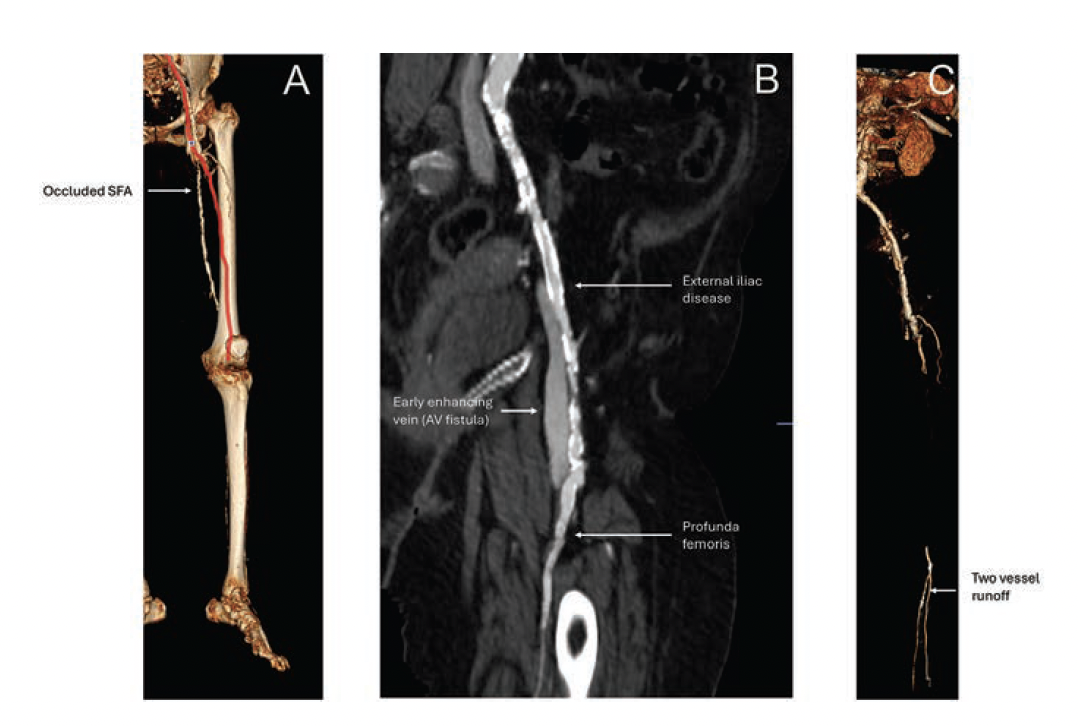

Approximately 1.5 years prior to consultation, the patient’s ankle-brachial indices were measured at 0.46 on the right and 0.24 on the left. Given her significant comorbidities and frailty, the patient was deemed unsuitable for further revascularization at that time by another department. However, her persistent and severe ischemic pain continued to be a major concern for the patient and her family. A CT angiogram (CTA) was obtained at our institution through another department, with the aim of identifying potential revascularization targets that could alleviate her symptoms. The CTA revealed severe diffuse bilateral vascular disease, including 60% to 70% stenosis of the distal aorta, severe stenosis of the right common femoral artery, occlusion of a right profunda-to-popliteal bypass graft and occluded native right superficial femoral artery, an occluded or severely stenotic right popliteal artery, and 2-vessel runoff to the right foot via the posterior tibial and peroneal arteries (Figures 1 and 2). On the left, there was multifocal mild-to-moderate disease in the common and proximal external iliac arteries, a patent external iliac stent, long-segment occlusion of the left superficial femoral artery, and 2-vessel runoff to the left foot via the posterior tibial and peroneal arteries (Figure 3).